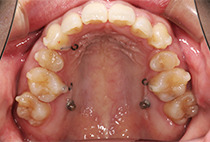

金属アレルギーがあるため、メタルフリーで治療できる【インビザライン】による抜歯矯正を選択されました。

矯正治療2年6ヶ月

30回

インビザライン、インプラントアンカー、美容治療